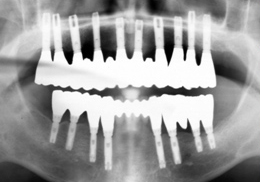

그림에서 보는 것처럼 턱뼈 안에 치아의 뿌리에 해당하는 매식체(티이타늄이라는 금속으로 되어있습니다)를 심고 그 위에 치아의 머리부분에 해당하는 보철물을 장착하는 시술법입니다.

임플란트 수술은 뼈속에 인공뿌리를 심는 1차수술과 잇몸바깥으로 치아를 만들 지대주를 연결하는 2차수술로 나눌 수 있습니다. 2차수술후 잇몸이 아문뒤 치관부분 보철물을 만들게 됩니다.

그동안 임플란트의 위치를 선정하기 위해 우선 이가 빠진 부위에 본을 뜬 후 임플란트의 위치를 결정하는 장치를 만들어 수술시 임플란트의 위치를 선정해 왔으나 때로는 임플란트의 방향과 각도가 부정확하게 심기는 경우가 있었습니다. 이에, 컴퓨터 단층촬영(CT)을 하고 그것을 3차원 컴퓨터 영상으로 변환한 후 잇몸뼈를 정확히 3차원 모델로 만들고 이 모델 상에서의 컴퓨터 가상 수술을 통해 위치가 정확히 결정된 “컴퓨터 유도장치”를 이용해 예상과 거의 100% 일치하는 방향과 각도로 정밀하게 임플란트를 심는 것이 가능해 졌습니다.